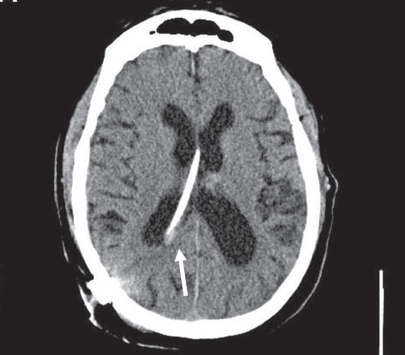

Kanwal Pratap Singh Raghav, MD; Kimberly Jegel, MD

A 59-year-old woman with past history of seizure disorder of unknown etiology since childhood came to hospital for incision and drainage of a right thigh abscess.

CT scan also showed conjugately deviated pupils to the right side, which is highly specific for seizures